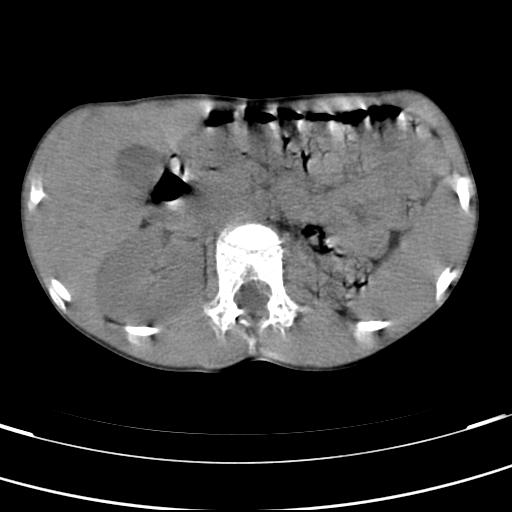

标题: PED3157:左肾缺如,请教脾脏的改变?、、

男孩,9岁。胃部不适。

脾脏位于左侧,但数个脾脏呈分离状态,左肾缺如,右肾代偿肥大。考虑多脾综合征。